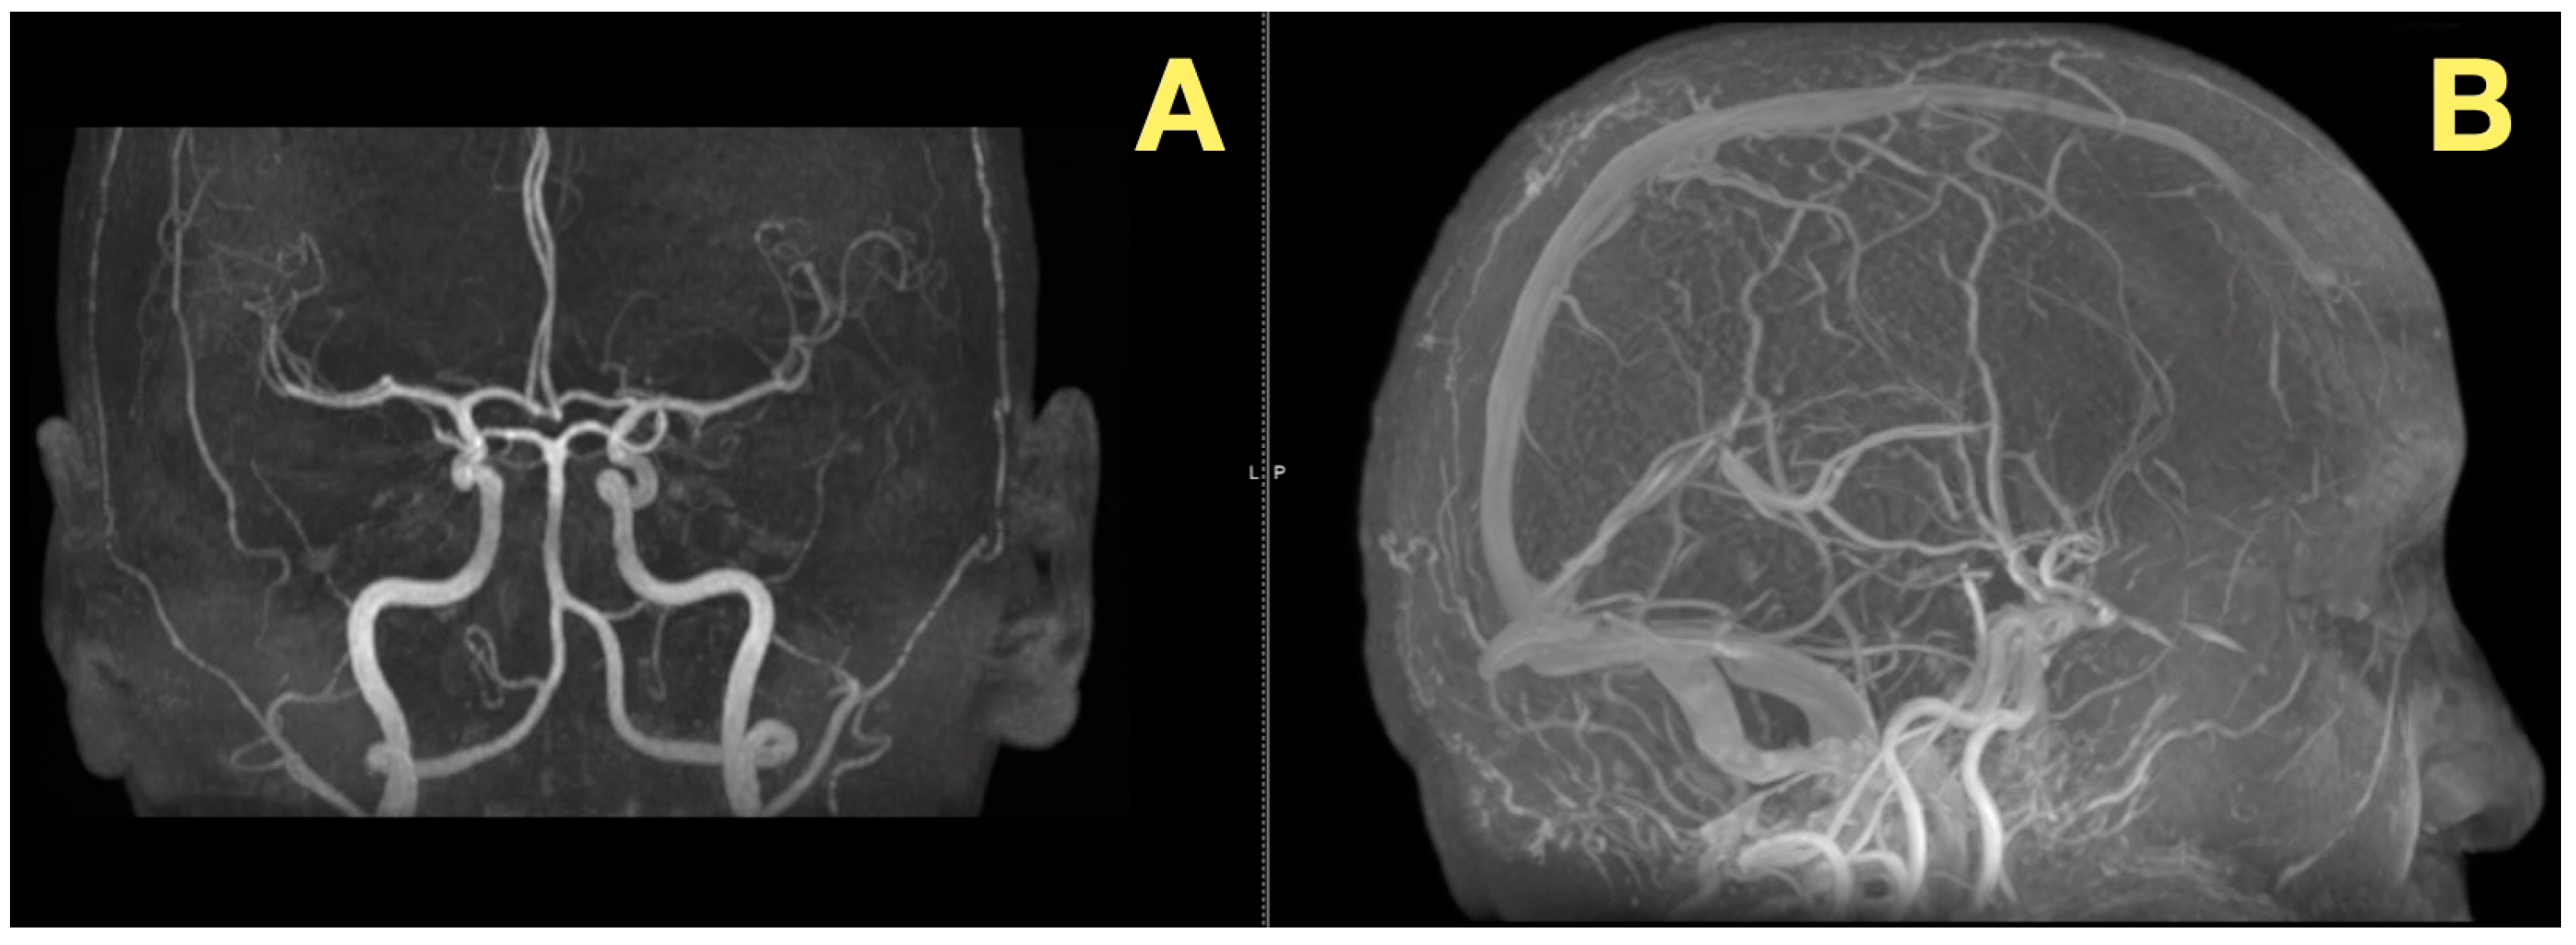

In addition to its rarity, the case also stood out due to the fact that all of the patient’s preoperative angiograms revealed a normal architecture of cerebral vasculature and no indication of aneurisms, arteriovenous malformations, or impaired venous outflow (Figure 2A,B). Further, the Circle of Willis was fully developed and symmetrically distributed, and the dural venous sinuses were unobstructed. As such, these studies ruled out vascular-related causes of intracranial hypertension and were consistent with a slowly expanding, avascular lesion.

Figure 2.

Preoperative vascular imaging. (A): Frontal MRA maximum-intensity projection: normal configuration of the circle of Willis without aneurysm or stenosis (B): Lateral MRA: preserved arterial flow and patent dural venous sinuses, excluding vascular or venous causes of intracranial hypertension; the pressure increase is attributable to CSF-outflow obstruction by the fourth-ventricular mass.